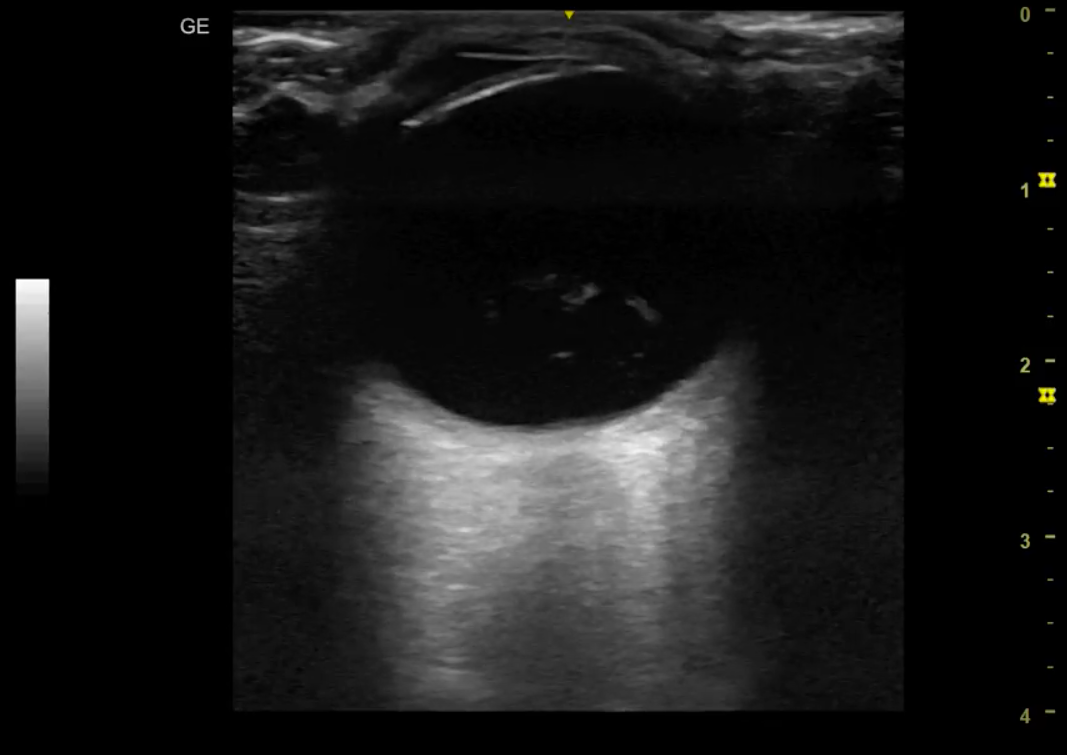

Hallazgos ecográficos

Se realiza ecografía ocular no reglada, donde se objetiva globo ocular anecoico con contenido heterogéneo hiperecogénico en polo posterior. Realce acústico posterior.

Desprendimiento de vítreo.

Tras el hallazgo ecográfico, se comenta el caso con Oftalmología de urgencias. Confirmar el desprendimiento de vítro del ojo derecho.